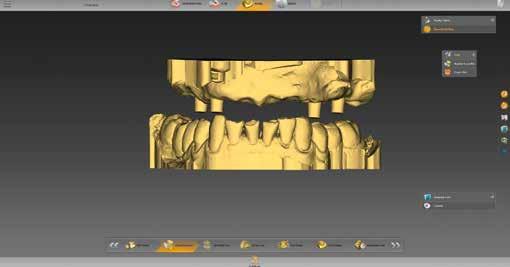

A tényleges munkát megelőzte a restauráció típusának kiválasztása. Kipipáltuk a multilayer és gingiva szavakat (6. ábra). Ezenfelül három hidat (14-16, 13-23, 24-26 régió) jelöltünk be, amelyek később a tercier részek lesznek. A „Modell” munkafázisban külön-külön megnézhettük a maxilla és mandibula mintáját (7. ábra), és ellenőrizhettük az intermaxilláris távolságot (8. ábra). A BioCopy alapján pontosan állíthattuk be a két mintát egymáshoz képest (9. ábra). Ezt követte egy nagyon fontos lépés: a felső állcsont gerinc-középvonalának berajzolása (10.

7. ábra: A maxilla mintája.

9. ábra: A BioCopy szkennelés alapján illesztjük a felső és alsó mintát. 6. ábra: Az adminisztratív fázisban meghatározzuk az alapbeállításokat, aktiváljuk a „multilayer” és „gingiva” mezőket.

8. ábra: Az intermaxilláris távolság ellenőrzése.